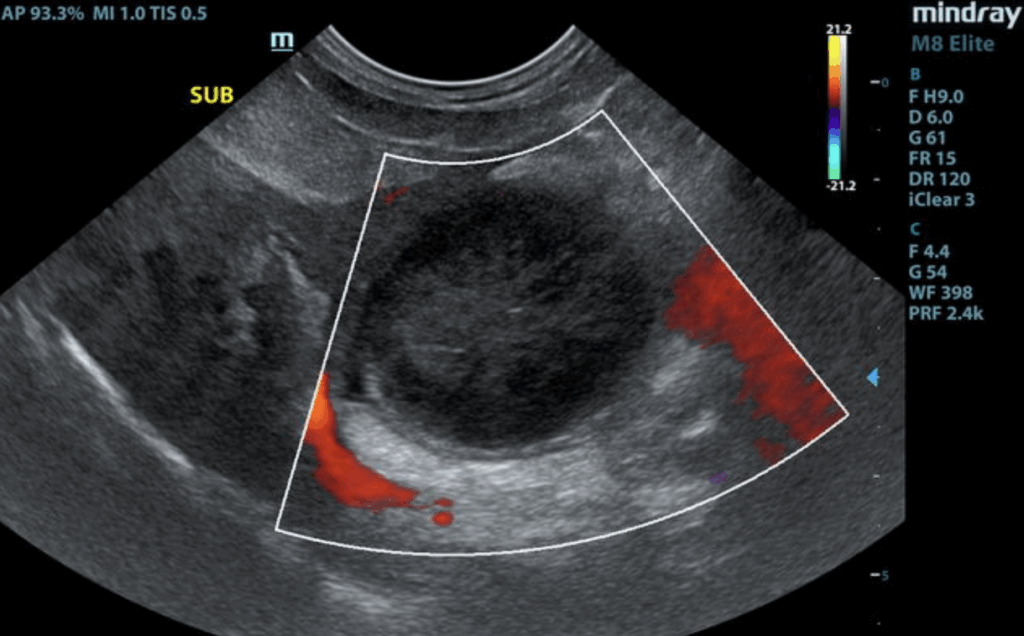

The liver presented enlarged in size. The parenchyma of the liver was subjectively normal in echogenicity compared to the spleen and renal cortices. The liver parenchyma was uniform with a mildly coarse echotexture. The capsule of the liver was symmetrically rounded to mildly swollen in margination. A solitary, small ventrocaudal thinly walled intraparenchymal cyst was present. The hepatic and portal vasculature were normal in appearance without signs of congestion. The gallbladder was distended in size with echogenic thickening of the gallbladder wall. There was biliary sludge that appeared to be non-mobile and organized. A stellate pattern to the organized biliary sludge was present. Regional pericholecystic omental inflammation without overt effusion was present. The common bile duct was not visualized.

• Gallbladder mucocele with peripheral inflammation.

Given gallbladder mucocele with pericholecystic inflammation and concurrent hepatopathy, cholecystectomy with hepatic biopsies assuming normal clotting status is warranted. However, given clinical history in this patient, surgical considerations may be limited. Likewise, even with surgery, overall prognosis is considered guarded given the possibility of mild bile leakage or possible emerging bile peritonitis. Gallbladder mucocele may be associated with Cushing’s syndrome or hypothyroidism. Hepato-gastrointestinal support would be reasonable. If surgery is elected in this patient, recheck echocardiogram indicated to assess anesthetic risk.

Abdominal ultrasound is diagnostic for a gallbladder mucocele. A gallbladder mucocele typically has a striated, stellate appearance and the material is not mobile. Common findings on ultrasound include a thickened gallbladder wall, free fluid and increased echogenicity of surrounding tissue in the gallbladder fossa. Gallbladder rupture is diagnosed on ultrasound by a discontinuity of the gallbladder wall, hyperechogenicity of the cranial abdominal fat, free peritoneal fluid, or a free, well-organised mucocoele within the peritoneal cavity.